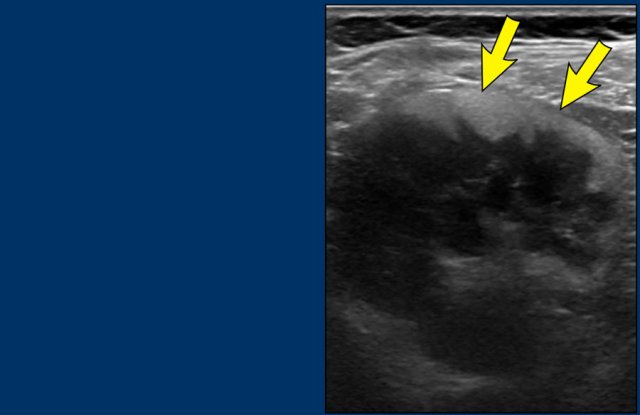

Although rhabdoid tumors are reported to demonstrate a subcapsular fluid collection, this can occur also as an uncommon manifestation in Wilms tumor, but these collections occur in absolute numbers more in Wilms tumor than in rhabdoid tumors.

Images

Two-week-old girl presenting with a mass in the left kidney.

A MRI of the brain at the time of initial diagnosis showed tiny lesions, possibly metastases (arrows).

An MRI four weeks later showed multiple brain and skull metastases.

The patient died two weeks later.